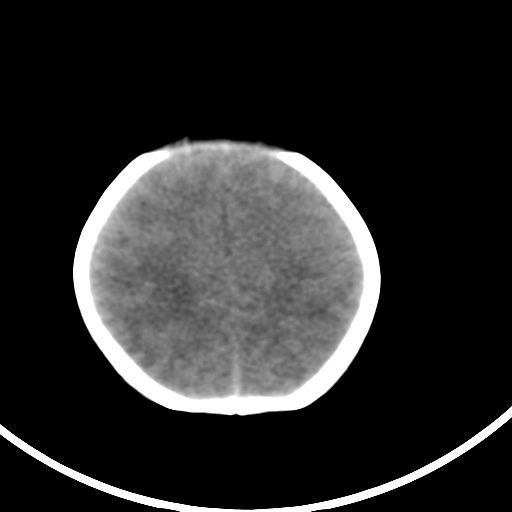

新生儿3天,超过预产期5天剖宫产,有缺氧病史,具体评分不详,现反应差,肌张力低,前囟平,原始反射存在,无苦闹等。

正常

颅底骨质影,正常颅脑表现。

正常颅脑表现。

kaolv小脑幕,后纵裂区蛛网膜下腔出血;轻度脑肿胀

未见明显异常

矢状窦旁征——支持蛛网膜下腔出血

颅脑ct平扫未见异常。

新生儿正常颅内表现

sah。